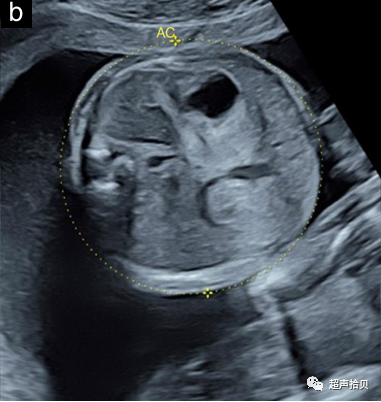

2. 应该获得一个图像来记录每个测量值。图1显示了适合于胎儿生物测量的静止图像示例;

图1标准胎儿生物测定法。超声测量:(a)头围(HC)、(b)腹围(AC)和(c)股骨长度(FL)。

腹围(AC)

• 在测量AC时,胎儿腹部的横切面应尽可能呈圆形,而胎儿的脊柱最好是在3点钟或9点钟的位置(良好实践证据)

• AC测量可以用椭圆法测量,也可以采用从腹部前后径(APAD)和横径(TAD)计算得出(良好实践证据)

1. AC 可以用椭圆游标直接在皮肤线的外表面测量(图 1b),也可以通过测量前后腹径 (APAD) 和腹横径 (TAD)计算得出 .